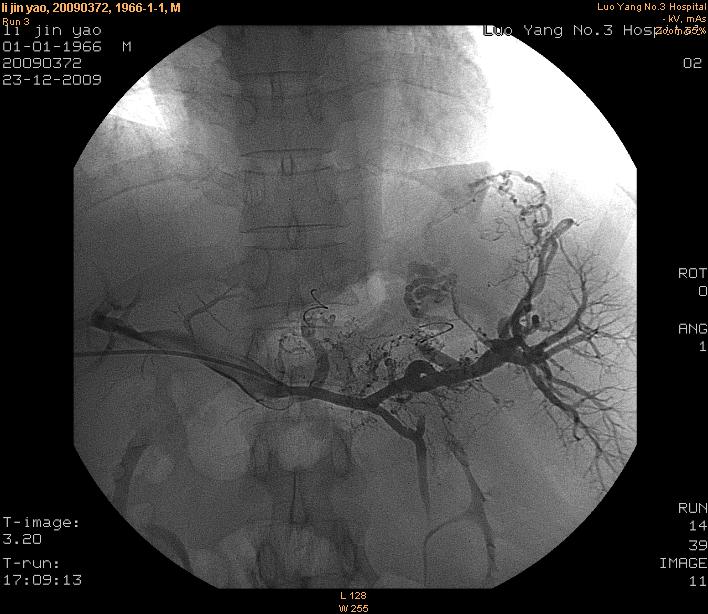

(七)、经皮经肝胃冠状静脉栓塞术

是消化内科开展的另一项治疗肝硬化并发消化道大出血的另一种血管介入技术,该技术通过经皮肤、经肝进入门静脉—胃冠状、胃短静脉—食管、胃底曲张静脉,注入栓塞剂(如无水酒精、弹簧圈),使曲张静脉闭塞,可有效防治出血,明显降低出血机率,疗效显著。可与内镜下曲张静脉套扎术、外科断流术综合运用,提高疗效。